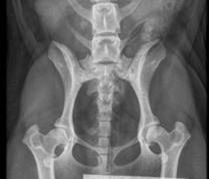

Miten lonkkaniveldysplasia todetaan?

Virallinen lonkkakuvaus voidaan tehdä koiralle 12 kuukauden iästä lähtien. Tutkimus tehdään rauhoitettuna, sillä lonkat

on vedettävä täysin suoriksi, mikä vaatii lihasten rentouttamista. Kuvat lähetetään eläinlääkäriasemalta Suomen Kennelliittoon, joka antaa virallisen lausunnon asteikolla A–E:

- A = terve

- B = lähes normaali

- C = lievä dysplasia

- D = keskivaikea dysplasia

- E = vaikea dysplasia

E-tuloksen saanutta koiraa ei saa käyttää jalostukseen missään rodussa. Koiran omistajan on tehtävä lähete Kennelliiton Omakoira-palvelussa ennen tutkimusta, että tulos saadaan virallisesti lausuttuna ja tulos tallennetaan jalostustietojärjestelmään